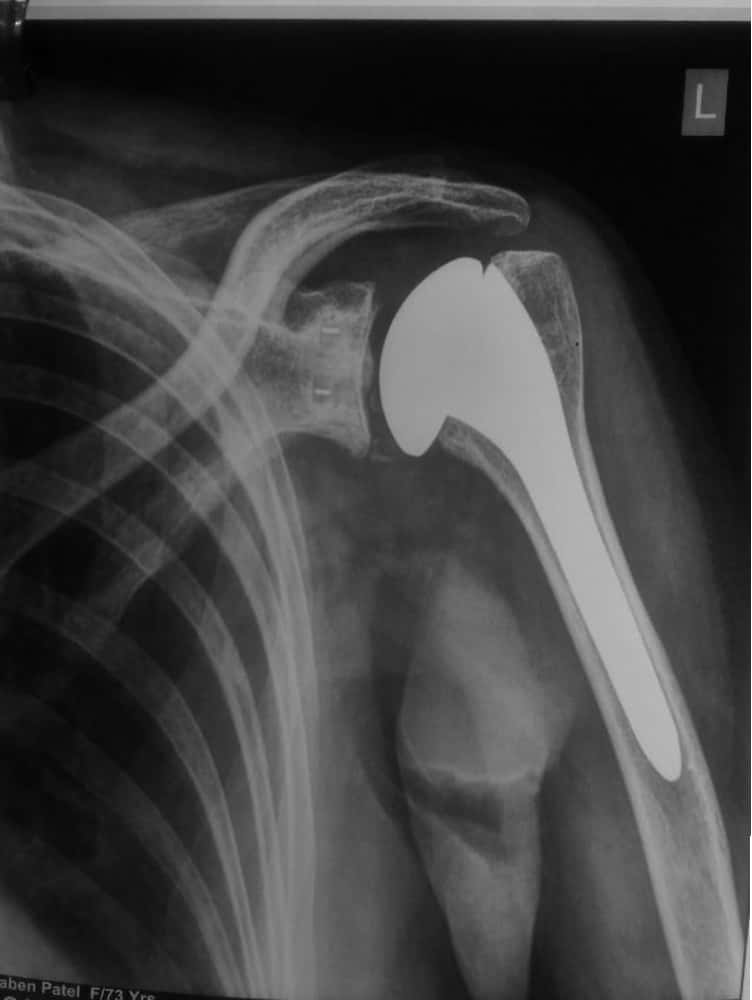

A Typical X-Ray of a well functioning Shoulder Replacement

Shoulder joint replacement (arthroplasty).Advanced arthritis of the glenohumeral joint can be treated with shoulder replacement surgery, in which the damaged parts of the shoulder are removed and replaced with artificial components, called prosthesis, just like a knee replacement which is indeed more common and more familiar for the patient!!

Complete wear or loss of normal smooth cartilage over the humeral head (Ball), Damaged cartilage over glenoid (socket), Replaced socket, replaced ballthis is how the replaced shoulder typically looks on an x ray!!